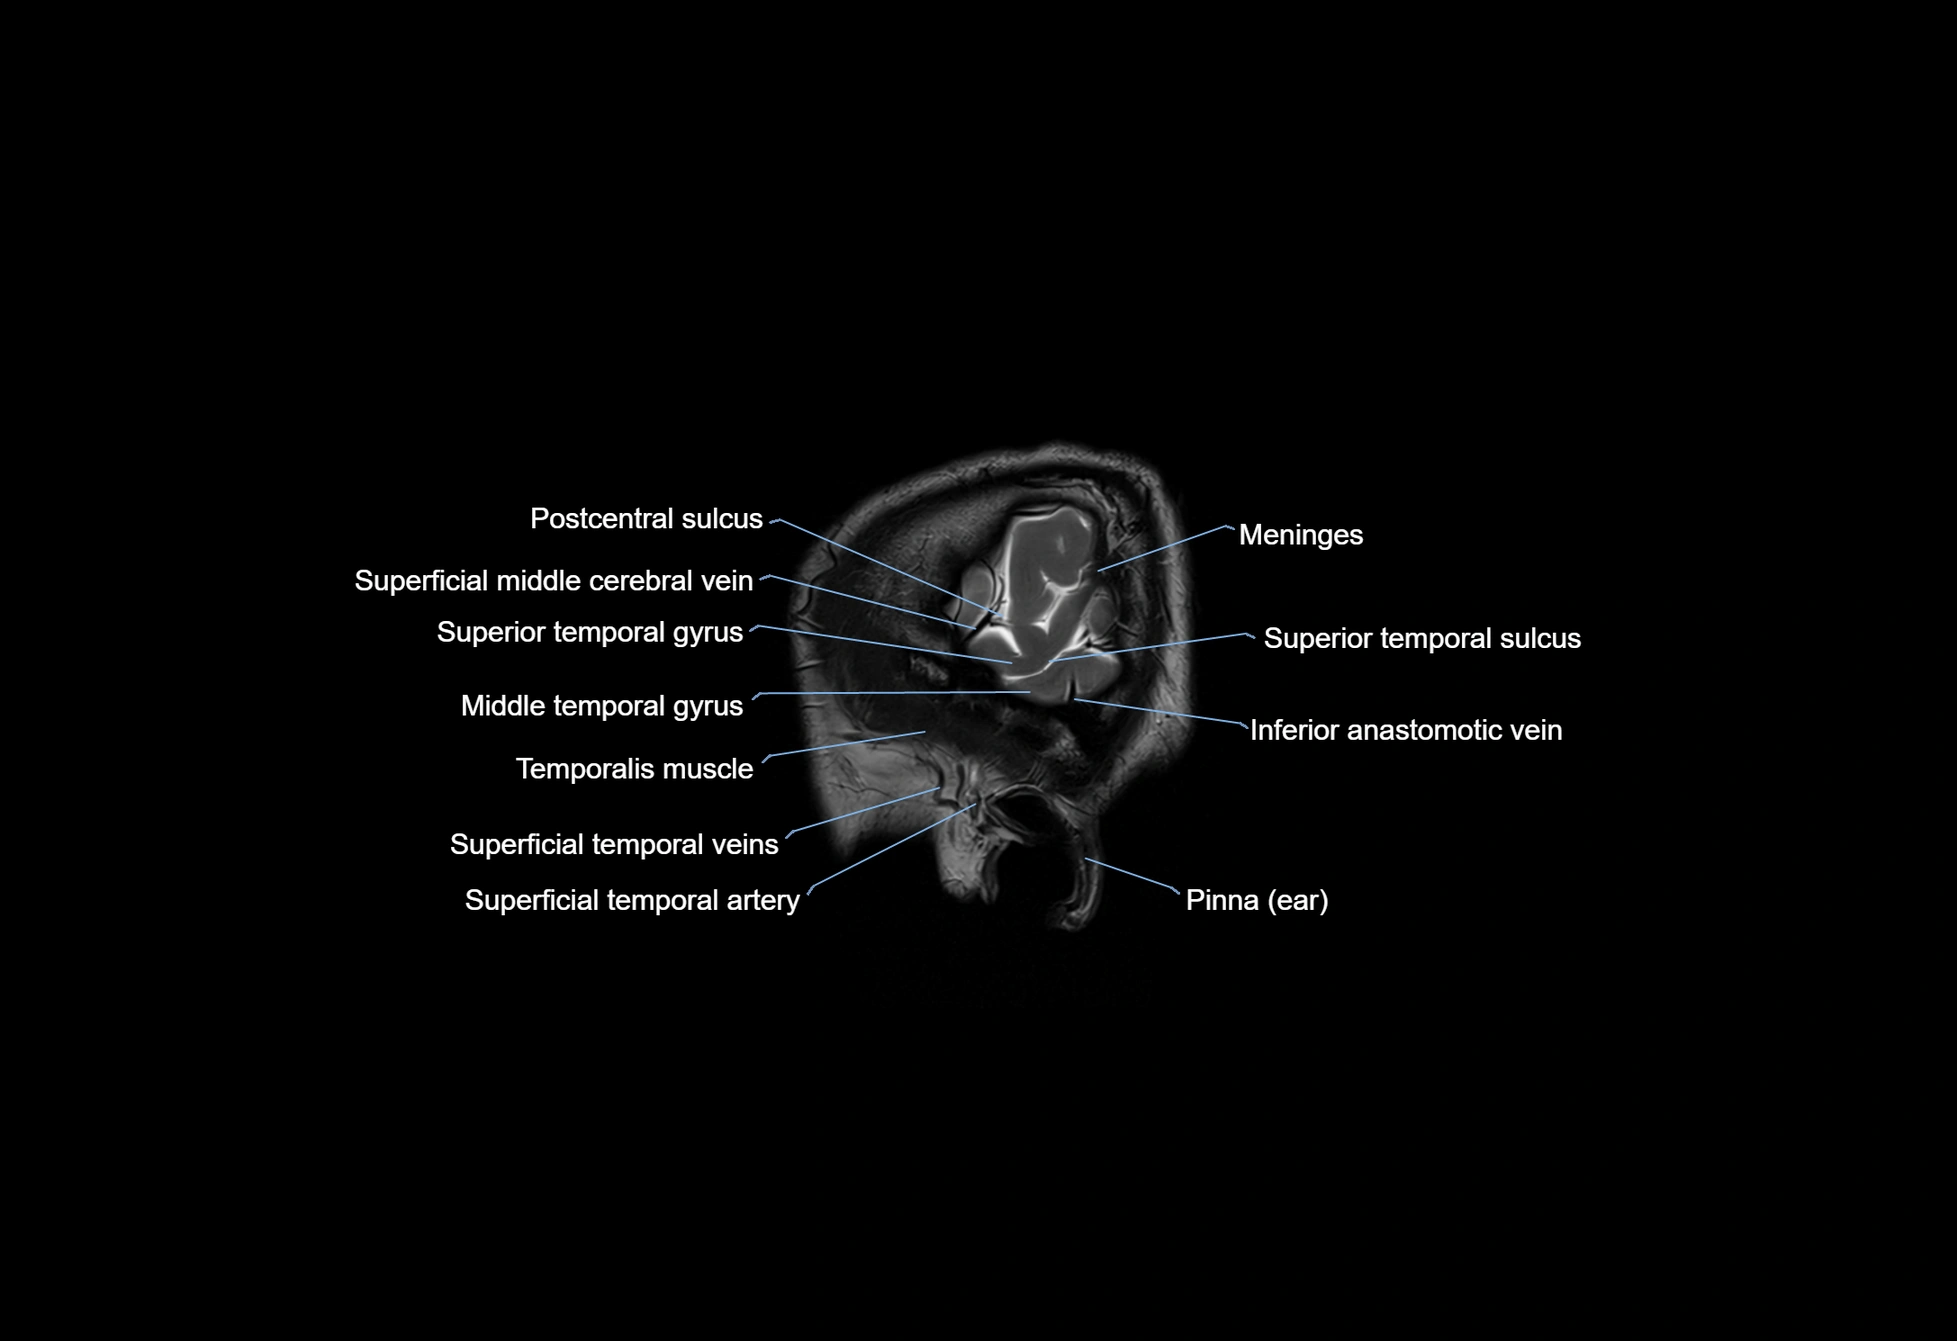

- Meninges

- Middle temporal gyrus

- Superficial middle cerebral vein

- Superior anastomotic vein

- Superior temporal gyrus

- Superior temporal sulcus